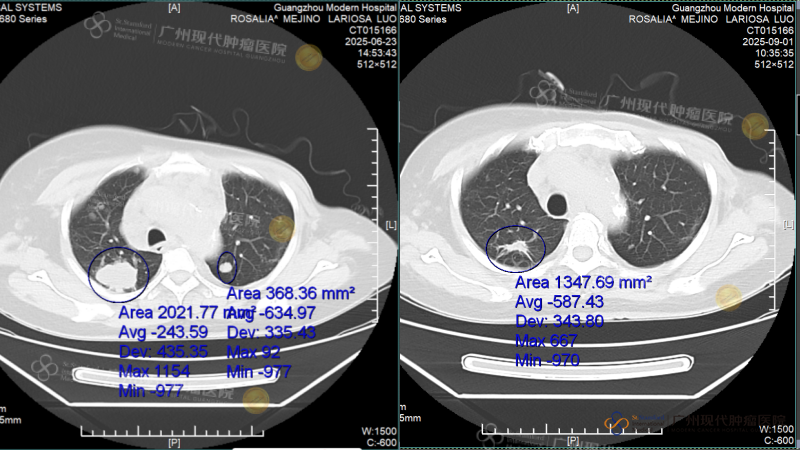

After the first treatment cycle, re-examination showed that the tumors in her body had shrunk by over 50% overall. The result after the second treatment cycle was what she herself called a "miracle": CT scans showed that all the tumors on her lumbar vertebrae had completely disappeared; one lung was completely clear; and the nodule in her neck that had been growing continuously was "melted" away. The latest examination report brought an almost complete victory: both lungs were essentially clear, with only minor remaining shadows continuing to fade, and both heart function and inflammation indicators had returned to normal.

CT scan comparison before and after treatment

(Left: Before treatment, 2023.6.23 Right: After treatment, 2023.9.1)